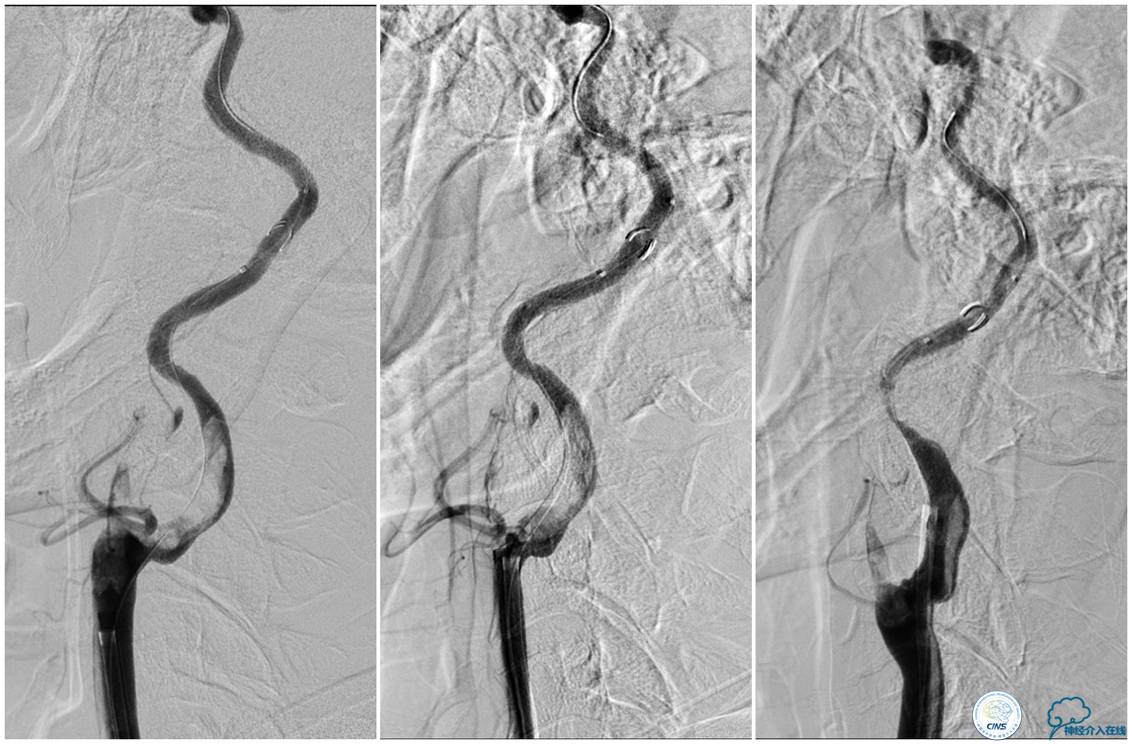

▼术后复查颈部CTA。

▼术后头颅CT复查:未见明显出血,左侧脑室旁可见少许低密度病灶。

术后第二天患者意识清,言语不清,右侧肌力恢复至3级,NIHSS评分2分,2周后右侧肌力5-级,NIHSS评分0分,行走出院。